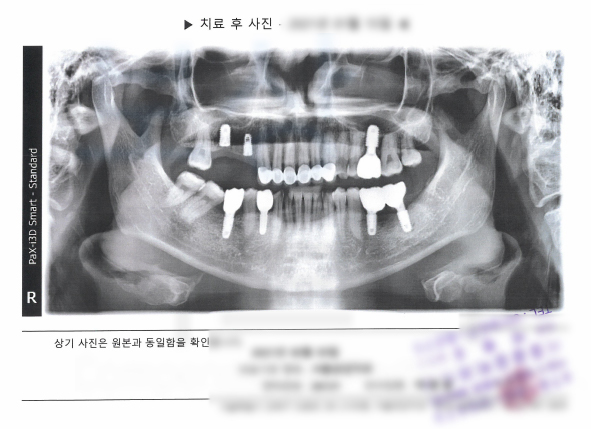

보상파트너는 의뢰인의 진료차트, 치아 파노라마 사진을 받아 분석을 진행하였고 보험금 지급의 가능성을 확인하였습니다. 보상파트너는 의뢰인의 임플란트 보험금 지급의 타당성을 증명하기 위해

의뢰인의 치아에 대해 K02.2 시멘트질의 우식증 K04.4 치수기원의 급성 근단 치주염 적용이라는 증거를 수집했고 약 2달간의 분쟁이 오간 결과 발치후 임플란트 보험금 인정 받을 수 있었습니다.